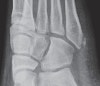

X-ray : 제5중족골 골절(Jones fracture)

Left image : The fracture line passes transversely across the bone.

Right image : A normal unfused 5th metatarsal base apophysis is aligned more longitudinally along the bone.

Developing apophysis는 시상면 방향으로 된 성장판을 가지는데, 골화 중심이 종축 방향이기 때문